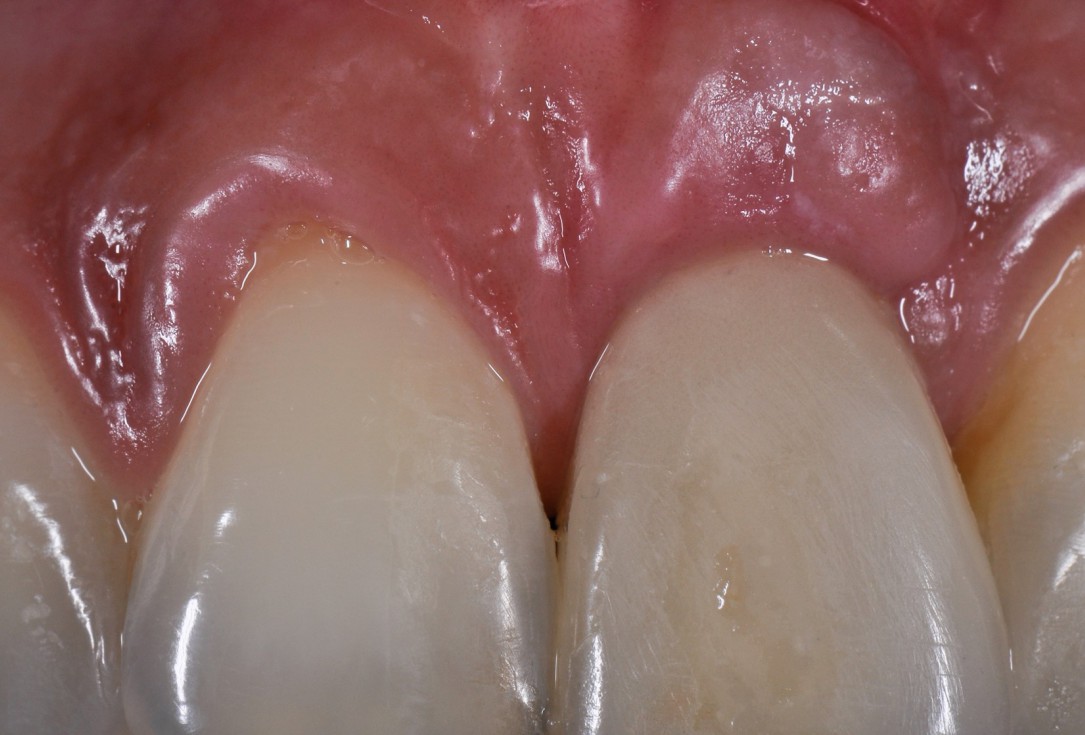

Immediate implant placement with cerabone® and mucoderm® - Dr. F. Rossi - Final outcome at 10 monthsImmediate implant placement with cerabone® and mucoderm® - Dr. F. Rossi